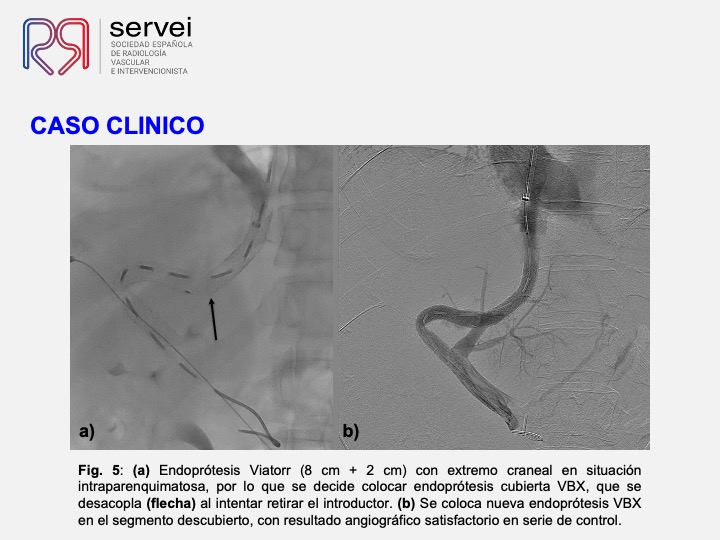

DIPS con técnica de “gun-sight”. Paciente con Síndrome de Budd-Chiari y eventual trombosis protésica